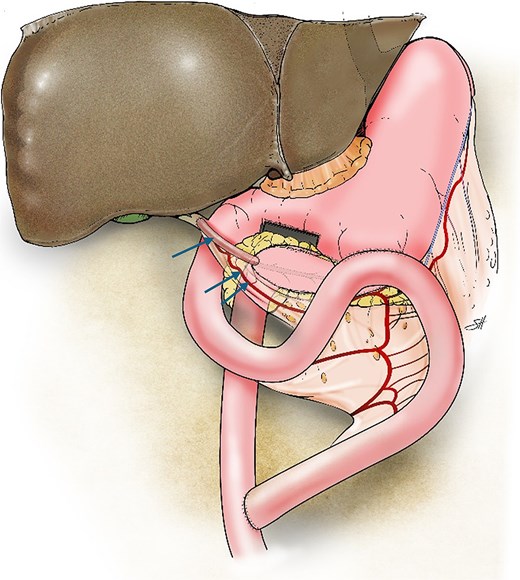

Finally, the proximal jejunal limb was used to construct side-to-side gastrojejunostomy on the posterior wall of the stomach by using the Endo-GIA stapling device (Covidien). The jejunojejunostomy was constructed 50 cm distal to the biliary anastomosis (Fig. 2).

Illustration of the triple bypass depicting reconstruction of the Roux-en-Y PJ, loop gastrojejunostomy, and the tubular gastric conduit (single arrow) created from the greater curvature of the stomach while maintaining the left gastroepiploic arcade (double arrows) to complete the end-to-side hepaticojejunostomy.

Here, we highlight a novel triple-bypass technique for managing chronic pancreatitis. We utilized the proximal jejunum to bypass the stomach, pancreas, and bile duct. An isolated vascularized tubular conduit was fashioned from the greater curvature of the stomach to facilitate a safe and tension-free hepaticojejunostomy. The gastric conduit, ~6 cm in length, was created while preserving the left gastroepiploic arcade. Dividing the right gastroepiploic artery allowed for the greater reach of the graft without compromising its blood supply. This maneuver was critical for successful tension-free anastomosis to the common bile duct.